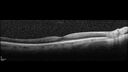

Latanoprost induced CME47 views89 year old man with CME from latanoprost that cleared within one month of stopping the medicationNov 23, 2025

Latanoprost induced CME57 views89 year old man with CME from latanoprost that cleared within one month of stopping the medicationNov 23, 2025

Latanoprost induced CME52 views89 year old man with CME from latanoprost that cleared within one month of stopping the medicationNov 23, 2025

Latanoprost induced CME60 views89 year old man with CME from latanoprost that cleared within one month of stopping the medicationNov 23, 2025